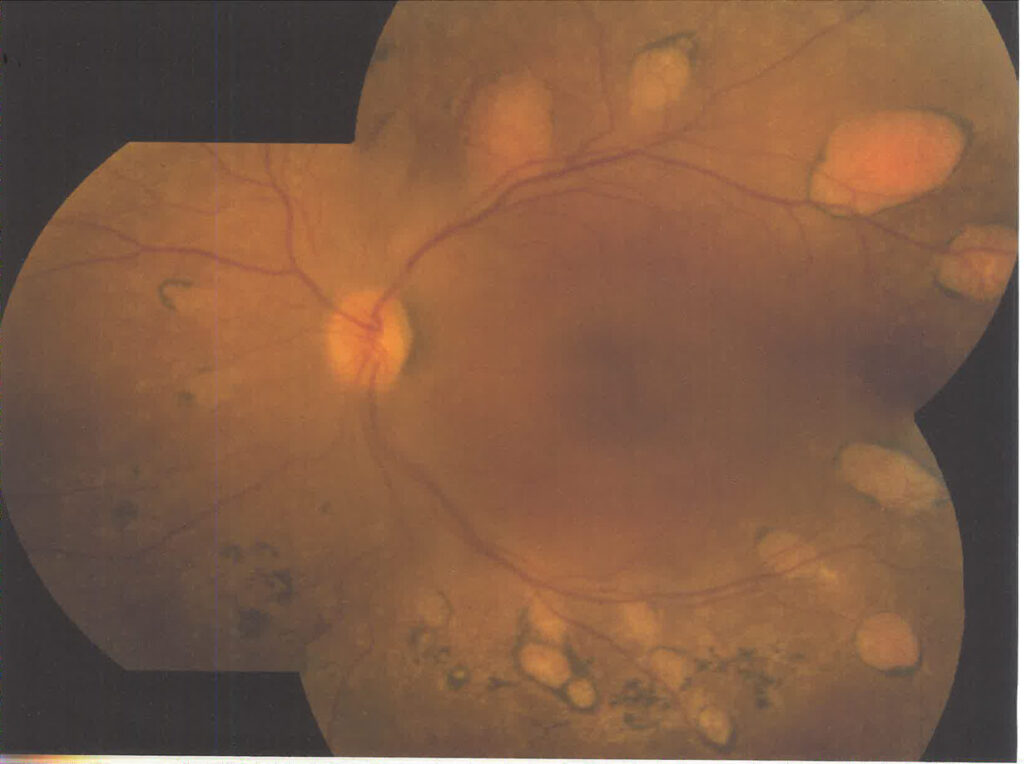

Discovery and Description of PolypoidalChoroidal Neovascularization

Polypoidalchoroidal neovascularization pertained to a new vascular abnormality identified in the choroid with a particular predilection for people of color, including African-Americans and Asian people. It also affected Caucasians with a separate set of risk factors, clinical manifestations, imaging characteristics, and treatments.

Yannuzzi LA, Wong D, Scassellati-Sforzolini B, et al. PolypoidalChoroidalVasculopathy and Neovascularized Age-Related Macular Degeneration. Arch Ophthalmol 117: 1503-1510, 1999